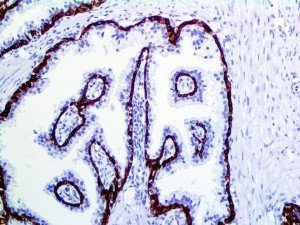

This activation induces inflammatory monocytes to highly express IL-6, starting a localized and then systemic cascade effect that results in hyperproduction of IL-6, which accelerates the inflammatory process. Because IL-6 also increases vascular permeability, excessive levels cause blood vessels to become very leaky. This, along with clotting factors released from vascular endothelial cells, stimulates the coagulation cascade, resulting in microthrombosis (tiny clots), which leads to ischemia and tissue death of the kidney, intestines, heart, liver, brain and extremities.